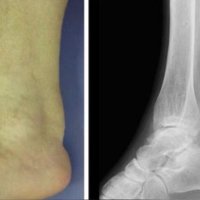

ACHILLES TENDON XANTHOMAS

Achilles tendon xanthomas are painless soft tissue masses occurring most commonly at the distal one-third of the tendon and are usually bilateral and symmetrical.

In plain radiograph, this condition appearas as soft tissue densities in the Achilles tendon.

Ultrasound reveals increased AP thickness of the tendon >7 mm in males and >6 mm in females, also loss of normal tendon appearance with multiple hypoechoic foci within the tendon.

MRI shows focal thickening of the tendon with increased AP diameter, loss of the normal anterior concavity of the tendon with speckled appearance of the tendon, hyperintense on T1- and T2-weighted images.